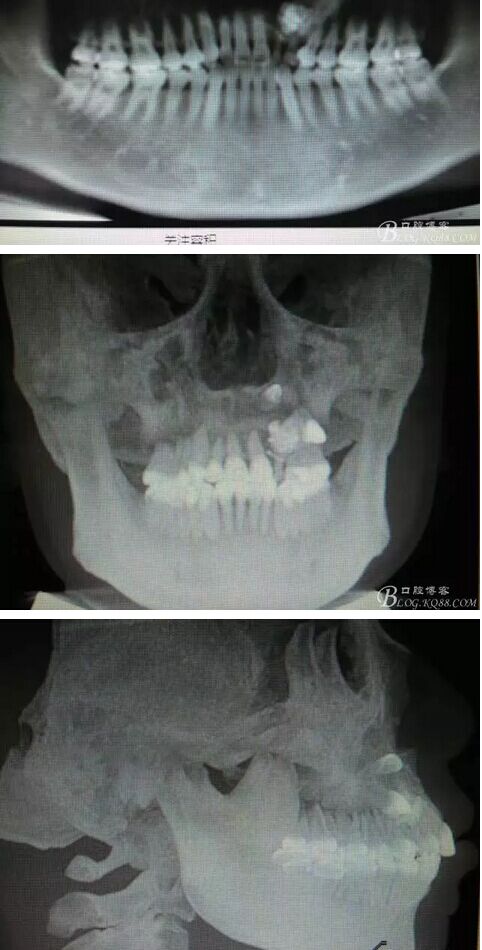

圖1。術前的CBCT影像檢查:22位于鼻底下方,23位于24、25的根方。左側乳Ⅱ、Ⅲ根方顯示囊性改變,囊腔內大量致密鈣化團塊,密度高。